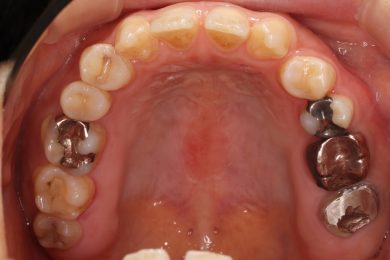

先天性欠如による上顎前歯欠損部にインビザライン術前矯正とインプラントを埋入した症例

初診時・インプラント・終了時